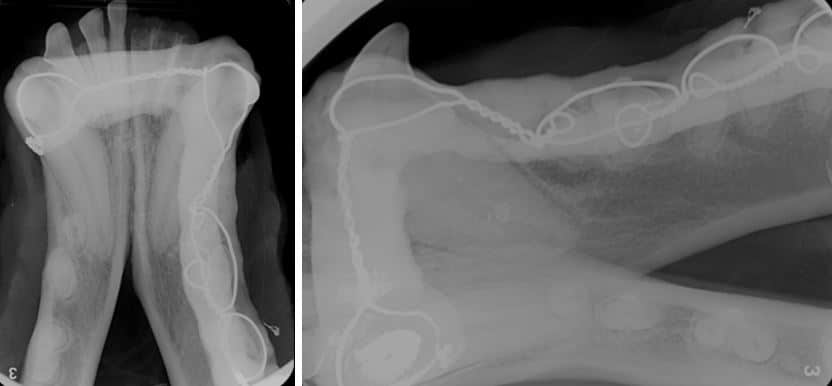

Figure 13 (A + B). Same patient as Figure 12. Intraoral splint comprised of interdental wire and composite resin placed following the extraction of the left mandibular incisors (301, 302, 303) and the reimplantation of the luxated canine tooth (304).

Figure 14 (A + B). Same patient as Figures 12 and 13. Dental radiographs two months following fracture repair. Interdental wiring and composite splint before removal. The previously luxated canine tooth was treated with root canal therapy at this visit, following splint removal.